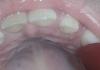

Всем привет, может кто-то разбирается, у дочки два дня назад была высокая температура 38.5, хныкала жаловалась что болят зубы, я смотрела ничего не увидела, вчера уже чувствала себя нормально, но ночью сегодня почувствовала у нее неприятный запах изо рта. Снова залезла посмотреть с фонариком и увидела что возле клыка все покраснело, а с обратной стороны вообще страшная картина какая-то. К стоматологу записались на послезавтра, раньше мест нет, но теперь сижу переживаю сильно, чтобы там гноя или еще чего не было...У дочки был полгода назад герпетический стоматит и я думаю может ли это он и быть или что-то другое? (Фото оставлю в комментариях)

У нас так стоматит был